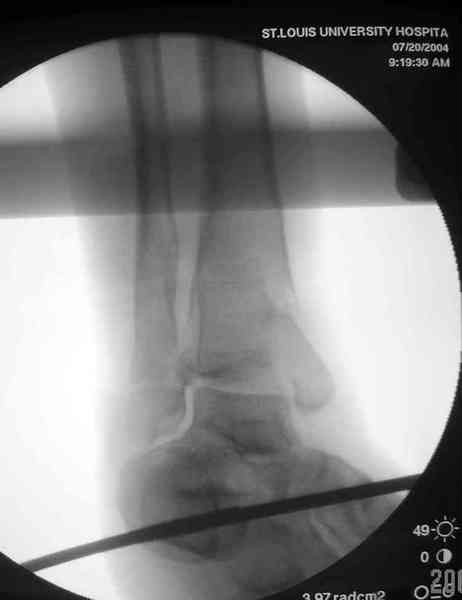

Здесь выставлена пара случаев перелома пилона, оба

случая леченные этапным наружным фиксатором.

Второй случай фиксирован аппаратом Илизарова.

Djoldas Kuldjanov, MD

Department of Orthopedic Surgery

St. Louis University Medical Center